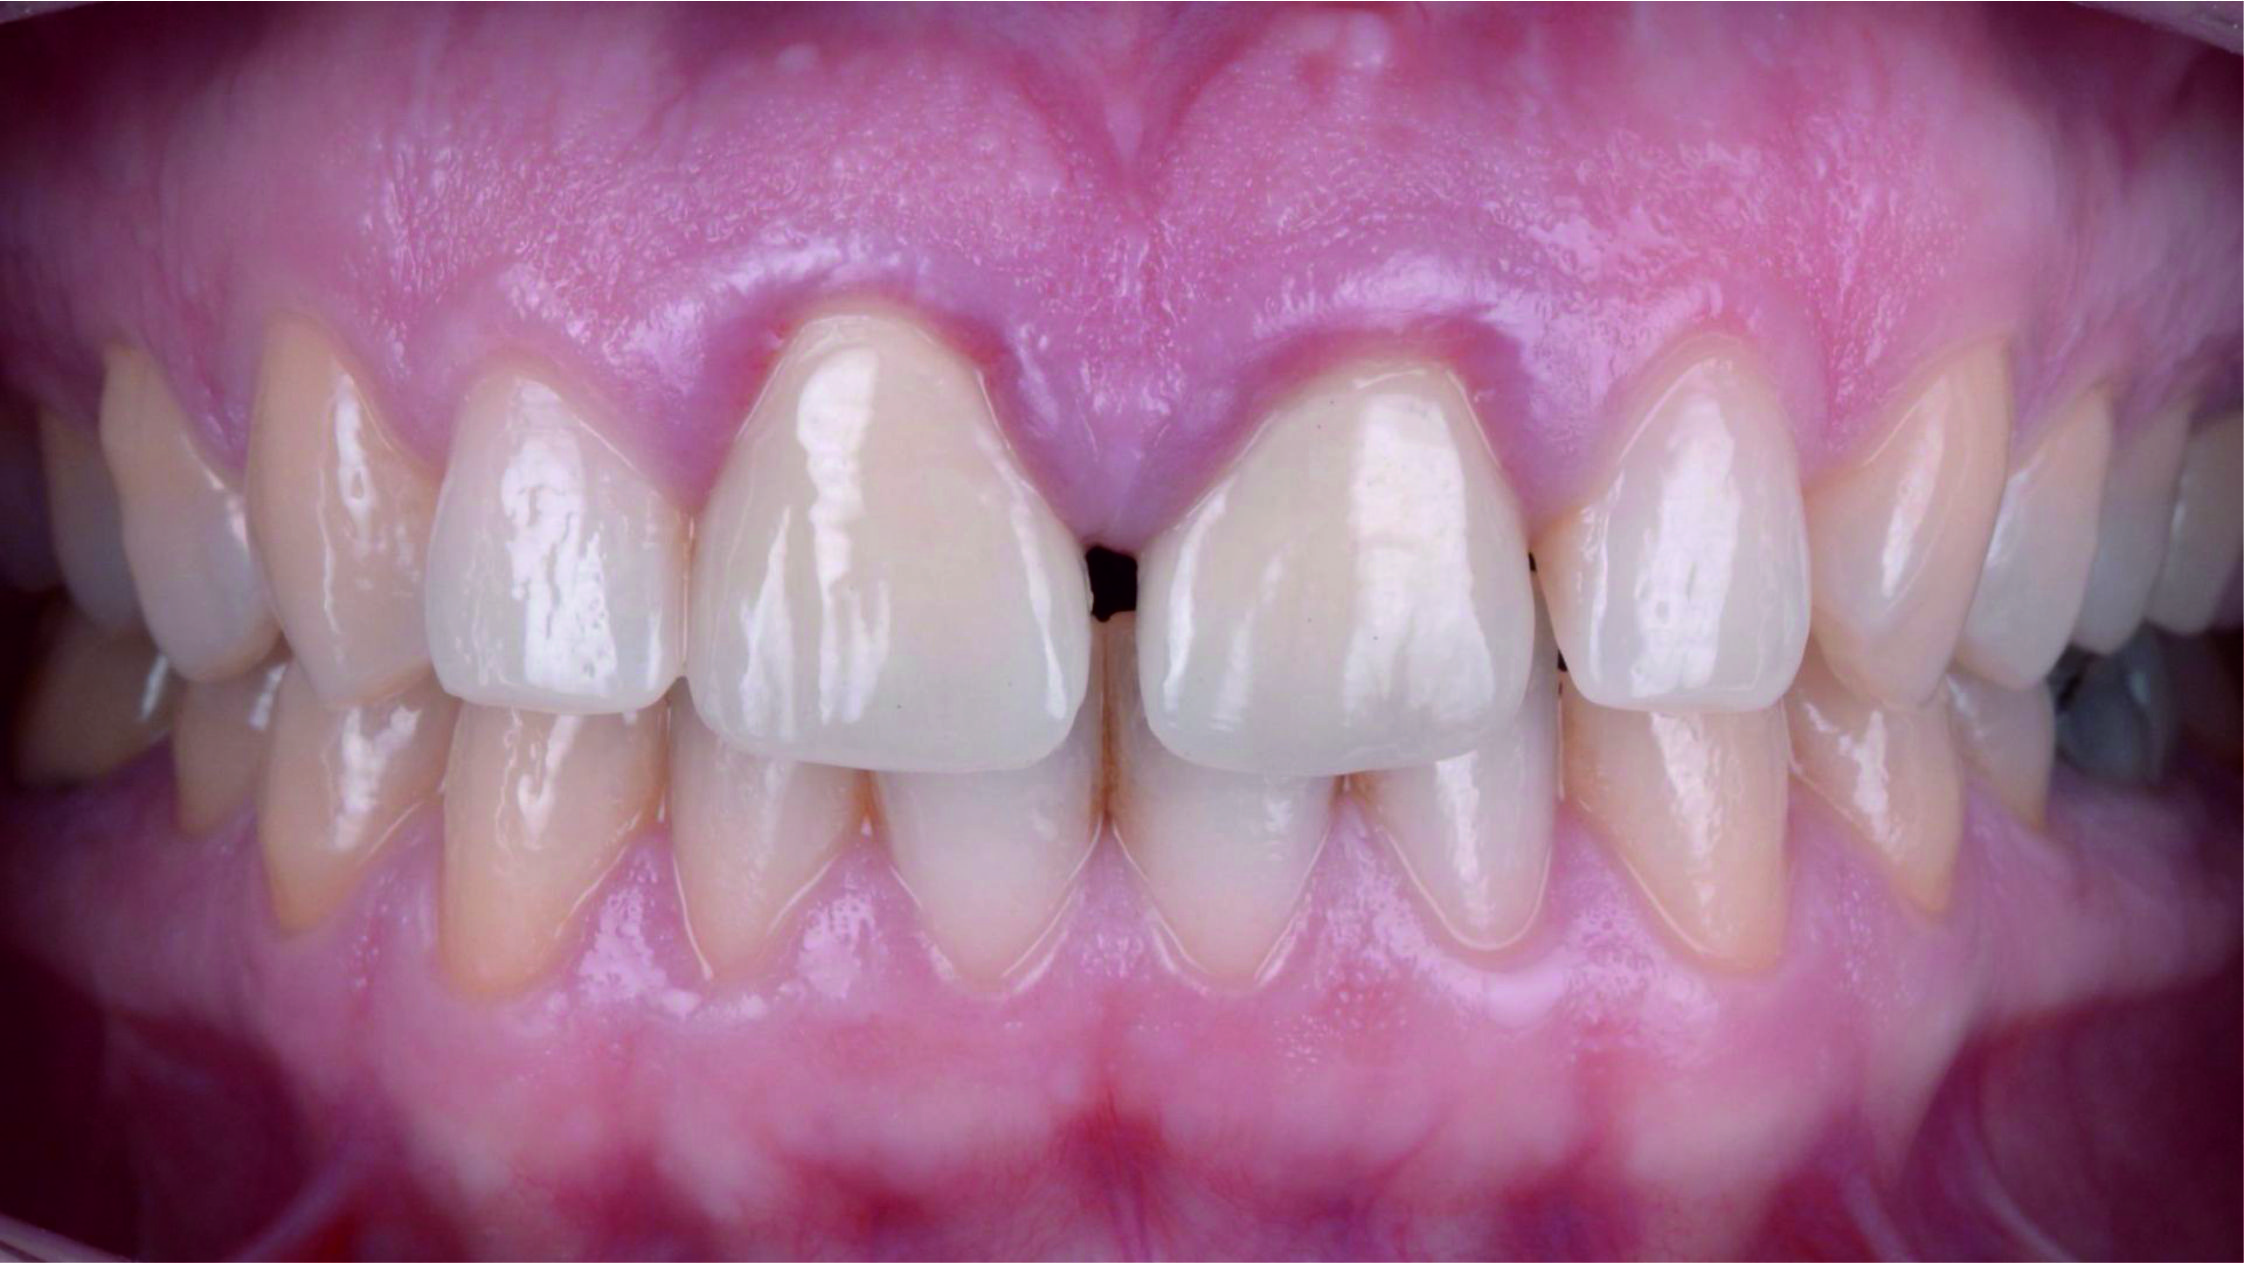

Фото 3. Внутрішньоротовий вигляд початкової ситуації.

Фото 16. Під час повторного візиту за місяць було видно, що ясна у зоні зуба 2.1 загоїлися в новому стабільному положенні.

Також була змінена форма медіальних поверхонь латеральних різців прямим методом за допомогою композита. Це дозволило оптимізувати ширину відстаней між фронтальними зубами. Також ми запропонували пацієнтці закрити діастему. Але пацієнтка вважає, що це – одна з її характерних особливостей, і тому вирішила її зберегти.

Фото 36. Вигляд під час повторного візиту за два тижні.

Фото 37. Новий профіль прорізування гарантує здоров'я ясен протягом тривалого часу.Фото 38. Порівняння з початковою ситуацією.

Фото 39. І кінцевий вигляд посмішки.

Фото 40. Посмішка задоволеної пацієнтки виправдовує всі наші старання.Верхні фронтальні зуби пацієнтки з посмішкою ясенного типу – це та ділянка, яка не прощає помилок, і де для отримання оптимального результату потрібно докласти максимум зусиль.